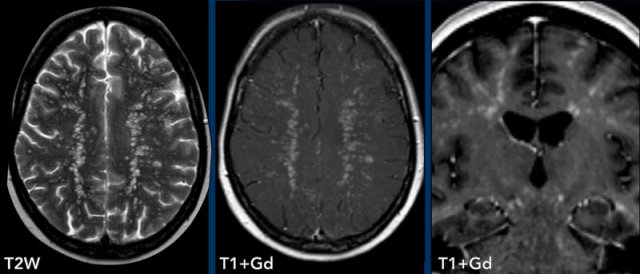

These examples show the advantage of FLAIR+Gd over T1W+Gd in a patient with lung cancer with cerebral metastases and carcinomatous meningitis.

Images

The FLAIR-image better shows the leptomeningeal enhancement around the pons (yellow arrow) and in the cerebellar foliae (black arrowheads).